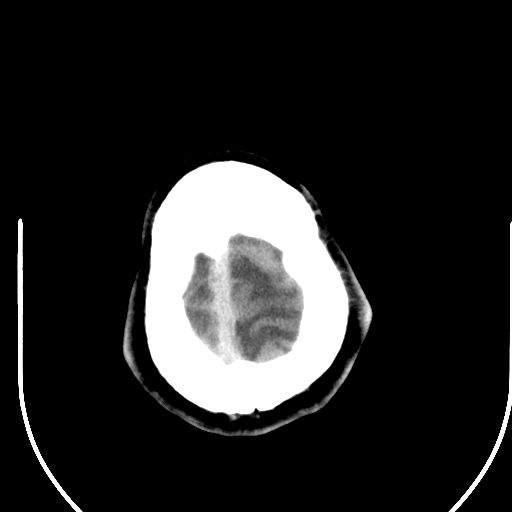

标题: CT25423:头部外伤意外发现右顶叶??? [打印本页]

标题: CT25423:头部外伤意外发现右顶叶???

ct值约13hu。

边缘清晰,没有占位效应,不像脑沟,结合ct值,软化灶可能吧

与脑沟没关系,小软化灶或陈旧性感染吧!

看样年纪不小了直接报腔梗,当然你要想报软化灶也是一样的

考虑右侧额叶巨腔隙灶;建议必要时行mri检查。

软化灶。